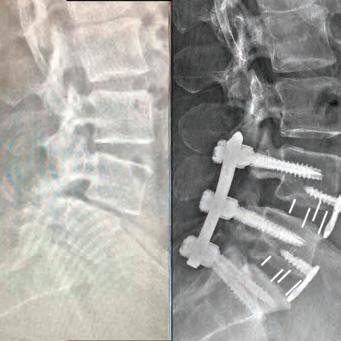

Our cover story this month features Dr. Stephen P. Courtney, a distinguished orthopedic spine surgeon whose commitment to his patients sets him apart in the medical community. Dr. Courtney’s career began humbly, working as an orderly in his teenage years, which sparked his passion for medicine. His academic and professional journey is nothing short of inspiring, having developed innovative spinal care technologies now patented under his name. Dr. Courtney applies a unique blend of hightech and high-touch approaches at Advanced Spine Center, ensuring that every patient receives the personalized care they deserve. Beyond his professional realm, Dr. Courtney is also an avid triathlete, illustrating the deep connection between physical endurance and personal health. Check out his story on page 8.

BOARD-CERTIFIED, FELLOWSHIP-TRAINED ORTHOPEDIC SPINE SURGEON PRACTICING FOR OVER 28 YEARS.

Inspired by the patients he’s cared for there, Dr. Courtney made education a priority. He was salutatorian of his high school class and went on to graduate summa cum laude from Northeast Louisiana University. While at Louisiana State University Medical School, he utilized his summer to perform spine biomechanical tests on human spine cadavers utilizing pedicle screws. Considered cutting edge biomechanics and technology at that time, most spine surgeons didn’t even know they existed yet. However, Dr. Courtney performed one of the fist biomechanical tests on those implants. It was a feat that earned him the Howmedica Biomechanic Award and the Louisiana Orthopedic Association Award. He also placed fourth in the World Congress for Student Research Competition.

Ths realization inspired Dr. Courtney to design, develop, biomechanically test, complete FDA testing and oversee quality control and validation on a host of tools he created. To date, Dr. Courtney has developed nine spinal product lines and obtained nine patents and 14 trademarks on spine related products.

SURGERY: L5/S1 360° LUMBAR FUSION

SURGERY: LEFT L5/S1 MICRODISCECTOMY

SURGERY: C4/C5, C5/C6, C6/C7 ACF (ANTERIOR CERVICAL FUSION)

SURGERY: L4/5, L5/S1 360° LUMBAR FUSION